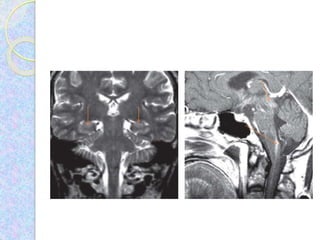

Neuroimaging

 MRI abnormalities provide clues for differential diagnosis with

other encephalitides, in terms of preferential sites and extent of

involvement

 Typically, MRI abnormalities are hypersignalT2 changes without

contrast enhancement involving the spinal cord, brainstem, thalamus,

limbic structures, and white matter during the non-comatose phase

 Both clinical forms of rabies in man have similar MRI features Lesions

in the brachial plexus, spinal cord, and nerve roots are already seen at

the prodromal stage as signal intensity abnormalities or enhancement.

 During the comatose phase, widespreadT2 hyperintense lesions in

the brainstem and forebrain can be seen; these are probably due to

virus-induced neuronal injury and superimposed hypoxic insult.